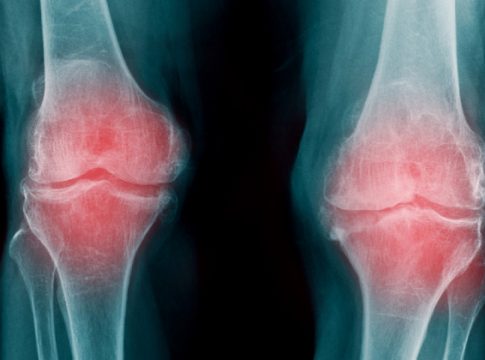

- Artrosis de rodilla

Este tipo de artrosis se caracteriza por el deterioro que genera el cartílago, provocando que se genere dolor con la actividad física, problemas para caminar y permanecer de pie. Esta enfermedad aparece en las personas antes de los 50 años de edad.